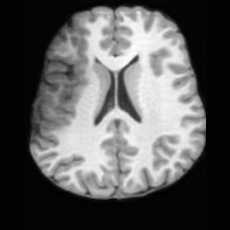

Healthy w/Lesion MaskPathologicalDifferencew/o LCGw/ LCG(a)Refer to captionRefer to captionRefer to captionRefer to captionRefer to captionRefer to captionHealthy w/Lesion MaskPathologicalDifferencew/o LCGw/ LCG(b)Refer to captionRefer to captionRefer to captionRefer to captionRefer to captionRefer to caption

Figure 7: Ablation study of Lesion Consistency Guidance (LCG). Without LCG, the generated pathological regions are indistinct and show weak pathological expression in both examples.

Lesion Consistency Guidance. Fig. 7 illustrates the impact of Lesion Consistency Guidance (LCG) for healthy-to-pathology editing. Without LCG, the generated lesion regions appear blurry around lesion boundaries, and the pathological patterns are less distinct, resulting in ambiguous lesion localization and weak pathological expression. Incorporating LCG produces lesions with more precise localization and well-defined shapes that better align with the given lesion masks, as well as textures and contrasts that exhibit stronger pathological characteristics. These results demonstrate that LCG effectively enforces lesion-aware conditioning, enhancing both spatial and semantic consistency of the generated pathological regions.